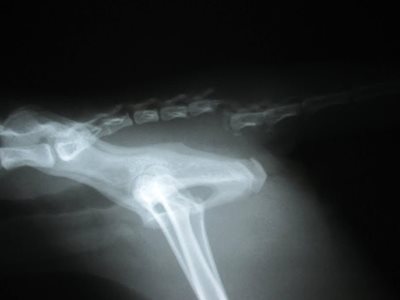

We x-rayed him and quickly found out what was going on. We confirmed that his tail was fractured and dislocated. However, what was more remarkable on the x-ray was the lack of intestines, stomach and liver. The abdomen looked quite empty! Where did they go? We then x-rayed the chest and found the missing organs. No wonder he was not feeling well.

I quickly called the speciality veterinary centre in Edmonton and got Bill Murray sent there ASAP for emergency surgery. This surgery involved moving the organs that had shifted into the chest back into the abdomen, repairing the hole in his diaphragm and restoring the negative pressure in his chest. It involved specialty equipment such as a ventilator to ensure he could breathe properly under anesthesia. The surgeons also amputated his tail where it was broken as well.